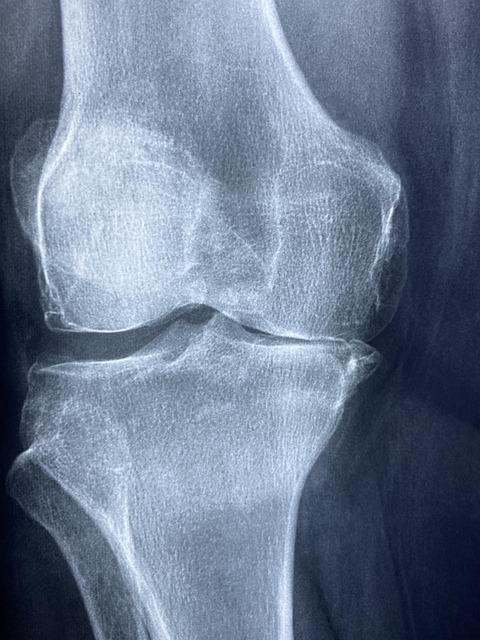

관절 통증의 핵심 원인은 바로 연골 마모입니다. 연골은 한 번 손상되면 자연 회복이 거의 되지 않는 조직인데, 40대 이후부터는 연골 재생 속도가 급격히 느려집니다.

그 결과 작은 충격에도 무릎, 어깨, 손가락 관절에서 뻐근함과 통증이 반복적으로 나타나게 됩니다.이는 노화가 진행되고 있다는 신호입니다.

근육은 관절을 보호하는 역할을 하는데, 이 보호막이 약해지면 관절이 체중과 충격을 그대로 받게 됩니다. 특히 무릎 관절 통증이 가장 먼저 나타나는 이유입니다.

무릎 관절의 경우 체중 1kg 증가 시 관절에는 약 3~4kg의 부담이 전달됩니다. 40대 관절통증이 무릎부터 시작되는 이유입니다.